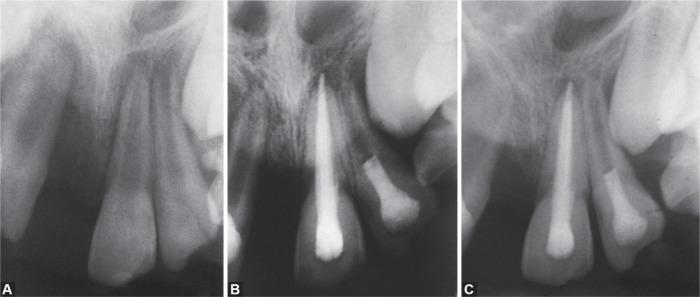

The aim of this paper is to present two methods of revascularization done in traumatized immature, nonvital anterior teeth using platelet-rich fibrin (PRF) and natural blood clot as a scaffold material. This was performed after disinfection of the root canal space using tri-antibacterial paste. In one tooth, PRF prepared from autologous blood was placed in the canal and in the other tooth, natural bleeding was induced to obtain a fresh blood clot. The patient was recalled regularly at 1, 3, 6, 9, and 12 months' interval for evaluation. After 12 months, on clinical examination, both teeth showed negative response to percussion and palpation tests but positive response to cold and electric pulp tests. On radiographic examination, the tooth treated with PRF exhibited comparatively faster root lengthening, complete closure of the root apex, more thickening of the root dentinal walls, and narrowing of root canal space compared to conventionally revascularized tooth. Nagaveni NB, Poornima P, Mathew MG, A Comparative Evaluation of Revascularization Done in Traumatized Immature, Necrotic Anterior Teeth with and without Platelet-rich Fibrin: A Case Report. Int J Clin Pediatr Dent 2020;13(1):98-102.

本文旨在介绍两种对受创伤的未成熟、无活力的前牙进行血管再生的方法,使用富含血小板纤维蛋白(PRF)和自然血凝块作为支架材料。这是在使用三联抗菌糊剂对根管空间进行消毒后进行的。在一颗牙齿中,将由自体血液制备的PRF置于根管内,而在另一颗牙齿中,诱导自然出血以获得新鲜血凝块。定期召回患者,间隔1、3、6、9和12个月进行评估。12个月后,临床检查发现,两颗牙齿对叩诊和触诊测试均呈阴性反应,但对冷测和牙髓电活力测试呈阳性反应。影像学检查显示,与传统血管再生的牙齿相比,用PRF治疗的牙齿表现出相对更快的牙根延长、根尖完全闭合、牙根牙本质壁增厚更多以及根管空间变窄。Nagaveni NB、Poornima P、Mathew MG,《富血小板纤维蛋白在创伤性未成熟坏死前牙血管再生中的应用比较评估:病例报告》。《国际临床儿科牙科学杂志》2020年;13(1):98 - 102。